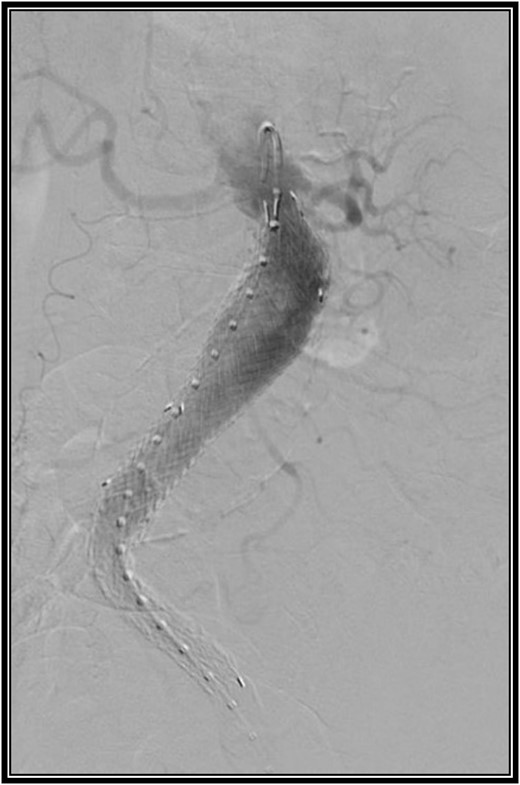

Given the patient has extensive comorbidities, it was decided to repair her AAA via an endovascular approach. Since she had complete occlusion of the right common iliac artery and lives a sedentary lifestyle without claudication symptoms, it was decided to perform a left AUI stent graft repair without FCB. This procedure also included a left common femoral endarterectomy given her significant atherosclerotic disease. Due to stenosis of her left common iliac artery, an 8 mm × 60 mm balloon was used to dilate this area to allow passage of the sheath. A 27 mm × 16 mm × 10 cm limb was modified to be used as the exclusion device. The device was deployed below the renal arteries. A 16 mm × 12 mm × 12 cm extension limb was placed, terminating above the left internal iliac artery. A type 1a endoleak was seen. A 28 mm × 3.3 cm aortic cuff was deployed just below the renal arteries. This resolved the type 1a endoleak. There was a small type 2 endoleak noted on the final angiogram (Fig. 2). The patient had a good recovery and was discharged on postoperative Day 1.

Intraoperative angiogram after placement of an aorto-uni-iliac stent graft.